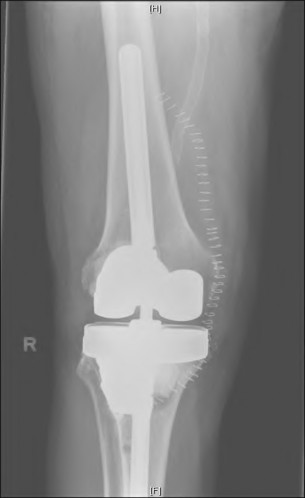

The radiograph demonstrates a periprosthetic femur fracture extending to the tip of the stem. The long spiral fracture is consistent with a loose implant. The bone stock is sufficient. Therefore, this fracture pattern would classify as a B2 using the Vancouver classification system. The Vancouver classification for periprosthetic femoral fractures is simple yet incorporates all the pertinent factors such a location, stem fixation, and bone stock. Type A is a trochanteric fracture- lesser or greater. These can be treated non-operatively usually and ORIF if symptomatic. Type B fractures are around or just below the stem and are subdivided into three types. Type B1 is a fracture with a well fixed stem.

The treatment is cable plating or allograft struts or a combination of the two. Type B2 is a fracture with a loose stem with good bone stock. The treatment is a cementless porous coated long stem atleast two diameter length past the

fracture site. Type B3 is a fracture with a loose stem and comminution. For younger patients, use cementless porous coated long stems with allograft struts. For older patients, consider a tumor prosthesis. Cement fixation is sometimes necessary Type C is a fracture well below the stem tip. These can be treated independently of the prosthesis.